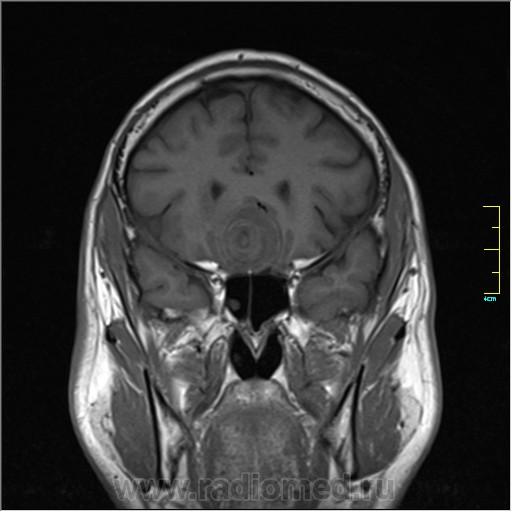

Пациентка направлена на исследование с диагнозом "Гипертонический криз", энцефалопатия неуточненная.

Cor T1:

частично функционирующая аневризма

Иначе говоря, аневризма с хронической геморрагией, т.к. мы видим фракции крови различного возраста.

По-моему, аневризма с пристеночными тромбами.

Постепенное пристеночное образование тромбов приводит к появлению типичного для аневризмы феномена -слоистости МР сигнала в полости аневризмы. Данная картина демонстрирует слоистый характер тромботических масс в полости аневризмы .Функционрирующая часть имеет низкий сигнал во всех режимах сканирования. Дополнительно-перифокальный отек.

А может более корректно интерпретировать как частично тромбированная аневризма... Уж коь речь идет о фракциях, ну то есть о тромбе по сути.... Ну и плюс перфокальный отек головного мозга (вероятнее цитотоксический+вазогенный).